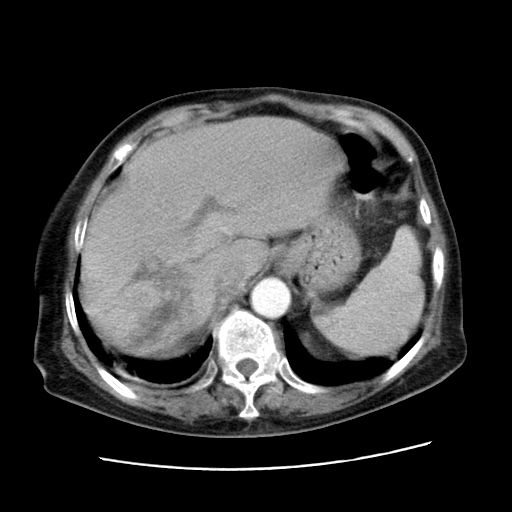

标题: CT25203:上腹部增强,看看

女,77.无不适

肝脏变异、异位胆囊,肝右叶肝内胆管结石并肝内胆管扩张。

肝右叶肝内胆管结石并肝内胆管扩张。

肝右叶肝内胆管结石并肝内胆管扩张

胆总管扩张

肝右叶肝内胆管结石并肝内胆管扩张。胆总管下段梗阻,考虑壶腹部占位。

右侧肝内胆管局限性扩张,其内密度不均匀,扩张的胆管壁增厚,考虑肝内胆管炎合并结石可能性大

肝右叶肝内胆管结石并肝内胆管扩张。胆总管下段梗阻,考虑壶腹部占位。支持